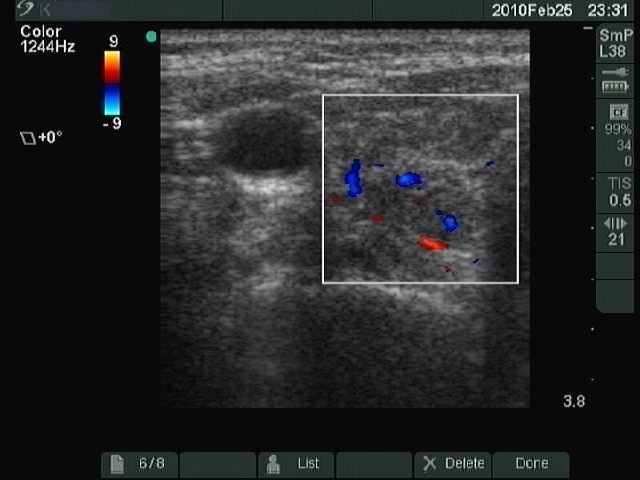

Chronic lymphocytic thyroiditis - Case 49. |

Clinical presentation: a 49-year-old woman with a newly discovered hypothyroidism (TSH 31.7 mIU/L) and a thyroid nodule in a previous sonographic report.

Ultrasonography: typical picture of Hashimoto's thyroiditis without any nodules.

Cytological report: benign Hashimoto's thyroiditis.